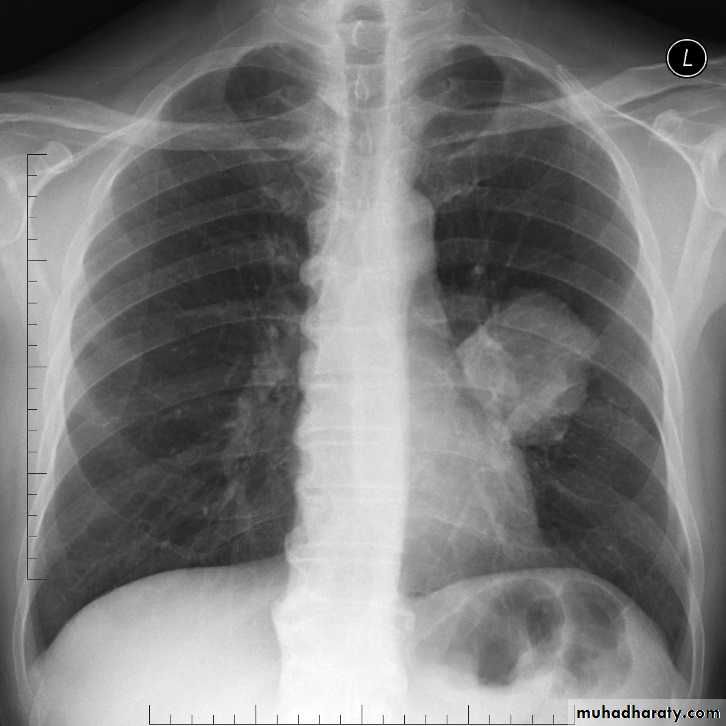

Lung cancer x ray

Pancoast Tumor